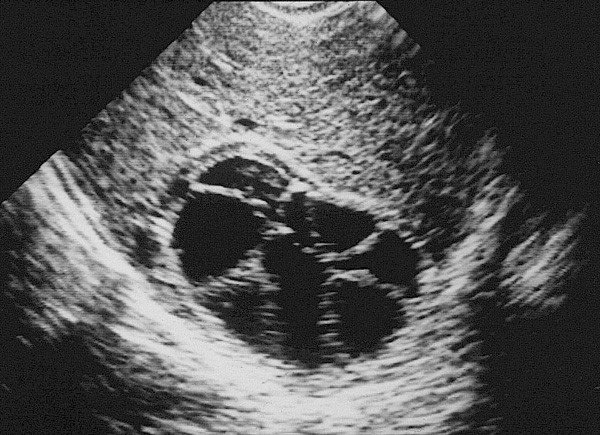

Transabdominal müayinələrdən fərqli olaraq US gel yerinə normal fizioloji məhluldan istifadə olunur. Ilk olaraq qaraciyər anatomik quruluşu müəyyən edilir (seqmentlər, damarların anatomiyası, öd yollarının variantları və s.) (şək.2)

Sonradan isə patoloji prosesin yerləşmə nahiyyəsi, yayılma dərəcəsi, damarlara olan münasibətini,invaziya dərəcəsini və  rezeksiya olunacaq sahənin adekvat olub olunmamasını müəyyən edilir.

Damarların anatomiyası və qan axının ölçülməsi rəngli Doppler müayinəsi ilə aparılır (şək.3).